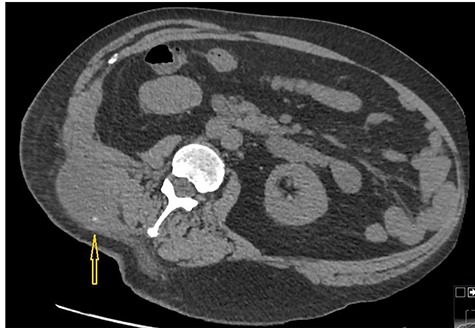

Because of previously identified calcification in the mass lesion and history of laparoscopic cholecystectomy, a non-contrast CT scan abdomen was obtained to ascertain if spilled gallstones were responsible for the recurrent abscess formation (Fig. 3).

Non-contrast CT abdomen: CT scan demonstrates a small hyper dense calculus in the abscess marked by an arrow. Here patient is lying in slightly left lateral position due to pain caused by the abscess.